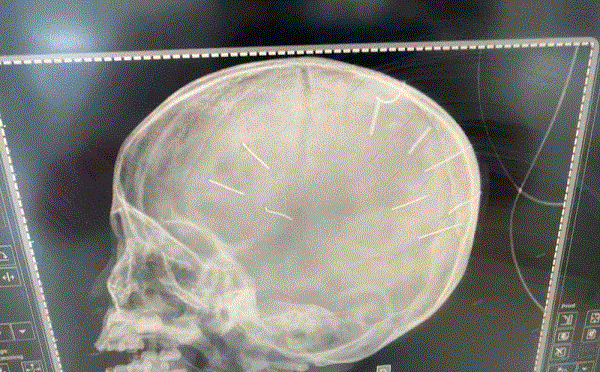

Công an huyện Thạch Thất, Hà Nội đã bắt được đối tượng hành hung dã man nữ chủ quán hải sản khiến nạn nhân chấn thương sọ não, vỡ gan, hôn mê.